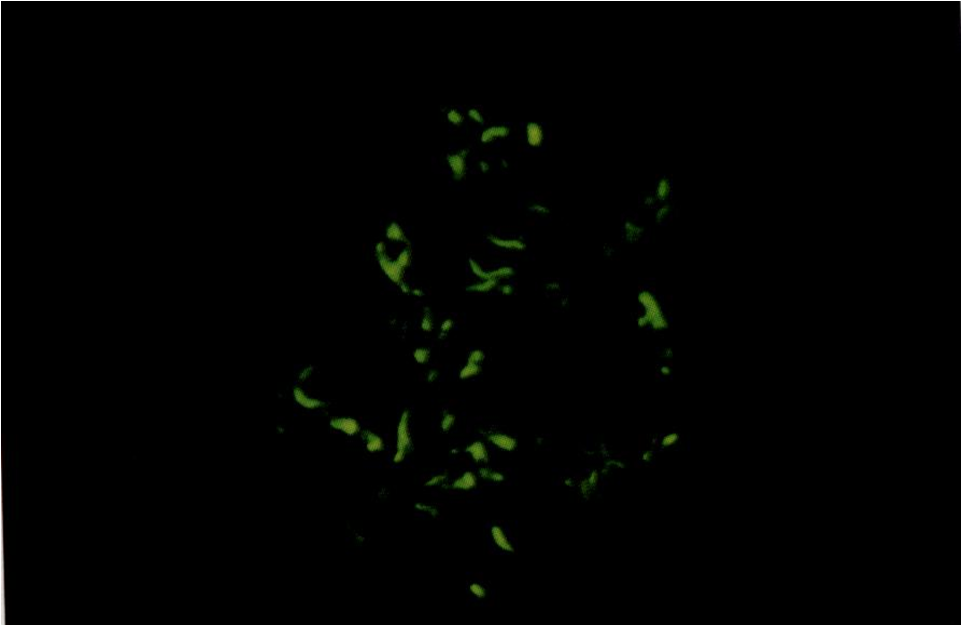

免疫病理检查可将本组疾病分为IgA肾病及非IgA系膜增生性肾小球肾炎。前者以IgA.沉积为主,后者以IgG或IgM沉积为主,均常伴有C3于肾小球系膜区、或系膜区及毛细血管壁呈颗粒状沉积。

电镜下在系膜区可见到电子致密物。 本组疾病在我国的发病率很高,在原发性NS中约占30%,显著高于西方国家。本病男性多于女性,好发于青少年。约50%患者有前驱感染,可于上呼吸道感染后急性起病,甚至表现为急性肾炎综合征。部分患者为隐匿起病。本组疾病中,非IgA系膜增生性肾小球肾炎者约50%患者表现为NS,约70%患者伴有血尿;而IgA肾病者几乎均有血尿,约15%出现NS。随肾脏病变程度由轻至重,肾功能不全及高血压的发生率逐渐增加。 本组疾病呈NS者,对糖皮质激素及细胞毒药物的治疗反应与其病理改变轻重相关,轻者疗效好,重者疗效差。